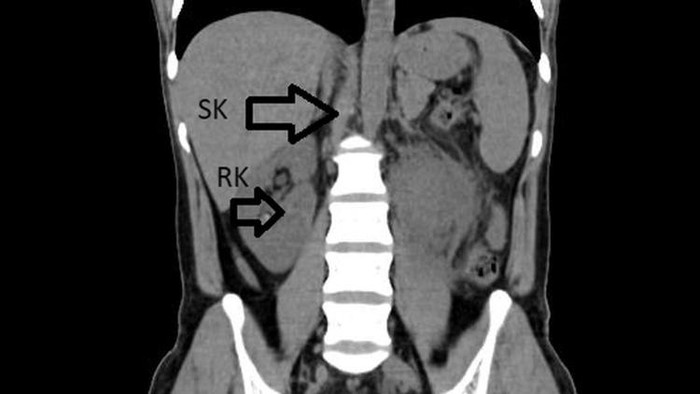

Pemeriksaan lanjutan menggunakan USG dan CT scan mengungkap temuan tak terduga. Dokter menemukan adanya ginjal ketiga atau ginjal supernumerary yang menyatu dengan ginjal kanan, membentuk struktur menyerupai tapal kuda.

Dikutip detikHealth dari Live Science, ginjal supernumerary merupakan kelainan bawaan yang terjadi saat perkembangan janin akibat pembelahan sel abnormal pada tali pusar yang kemudian membentuk ginjal tambahan.

Kondisi ini terkadang dapat memicu infeksi ginjal, meski dalam banyak kasus tidak mengganggu fungsi ginjal dan sering kali tidak terdeteksi.